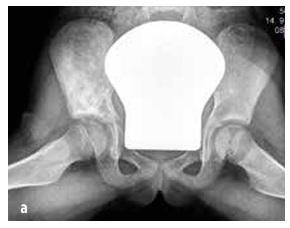

Септичний артрит зустрічається в 50 % випадків у дітей віком до двох років, а в 75 % випадків уражаються суглоби нижніх кінцівок (коліно > стегно > гомілка) (див. малюнок № 4). Остеомієліт найчастіше локалізується в метафізі.

Про інфекцію кістки або суглоба слід думати у дитини з раптовим розвитком: лихоманкою, незрозумілим кульганням та/або аномальним положенням кінцівки, відмовою використовувати кінцівку, обмеженням обсягу рухів, м’язово-скелетним болем ± місцевим болем при пальпації суглоба або кістки та набряком з почервонінням (див. малюнок № 4). CAVE маленькі діти локалізують біль неточно (наприклад, біль переноситься з стегна в область коліна).

Зображення № 4

Клінічні дані при септичному артриті